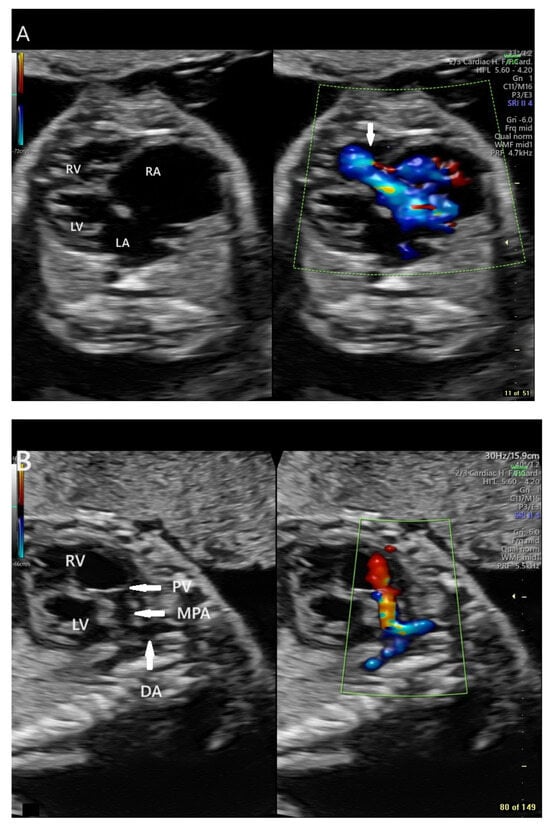

At cardiology follow-up at 30 6/7 weeks gestation, fetal echocardiography demonstrated recurrent fetal tachycardia with heart rates of 194 bpm, alternating with sinus vs. atrial rhythm with a rate of 152 bpm. The fetus was in tachycardia approximately 40% of the time. Right ventricular function was decreased when not in tachycardia. There was increasing cardiomegaly (increase in CT area ratio to 0.53 from 0.46), loss of antegrade pulmonary blood flow, continued severe tricuspid insufficiency, and marked pulmonary insufficiency, with retrograde flow in the ductus arteriosus. There was also evidence of hydrops fetalis with fetal ascites and pericardial effusion (Figure 3).

Figure 3. Echocardiographic sagittal still frame image of the fetal chest and abdomen demonstrating ascites and pericardial effusion (arrows) in the setting of early fetal hydrops at 30 6/7 weeks gestation (GE Voluson E10 Imaging System).